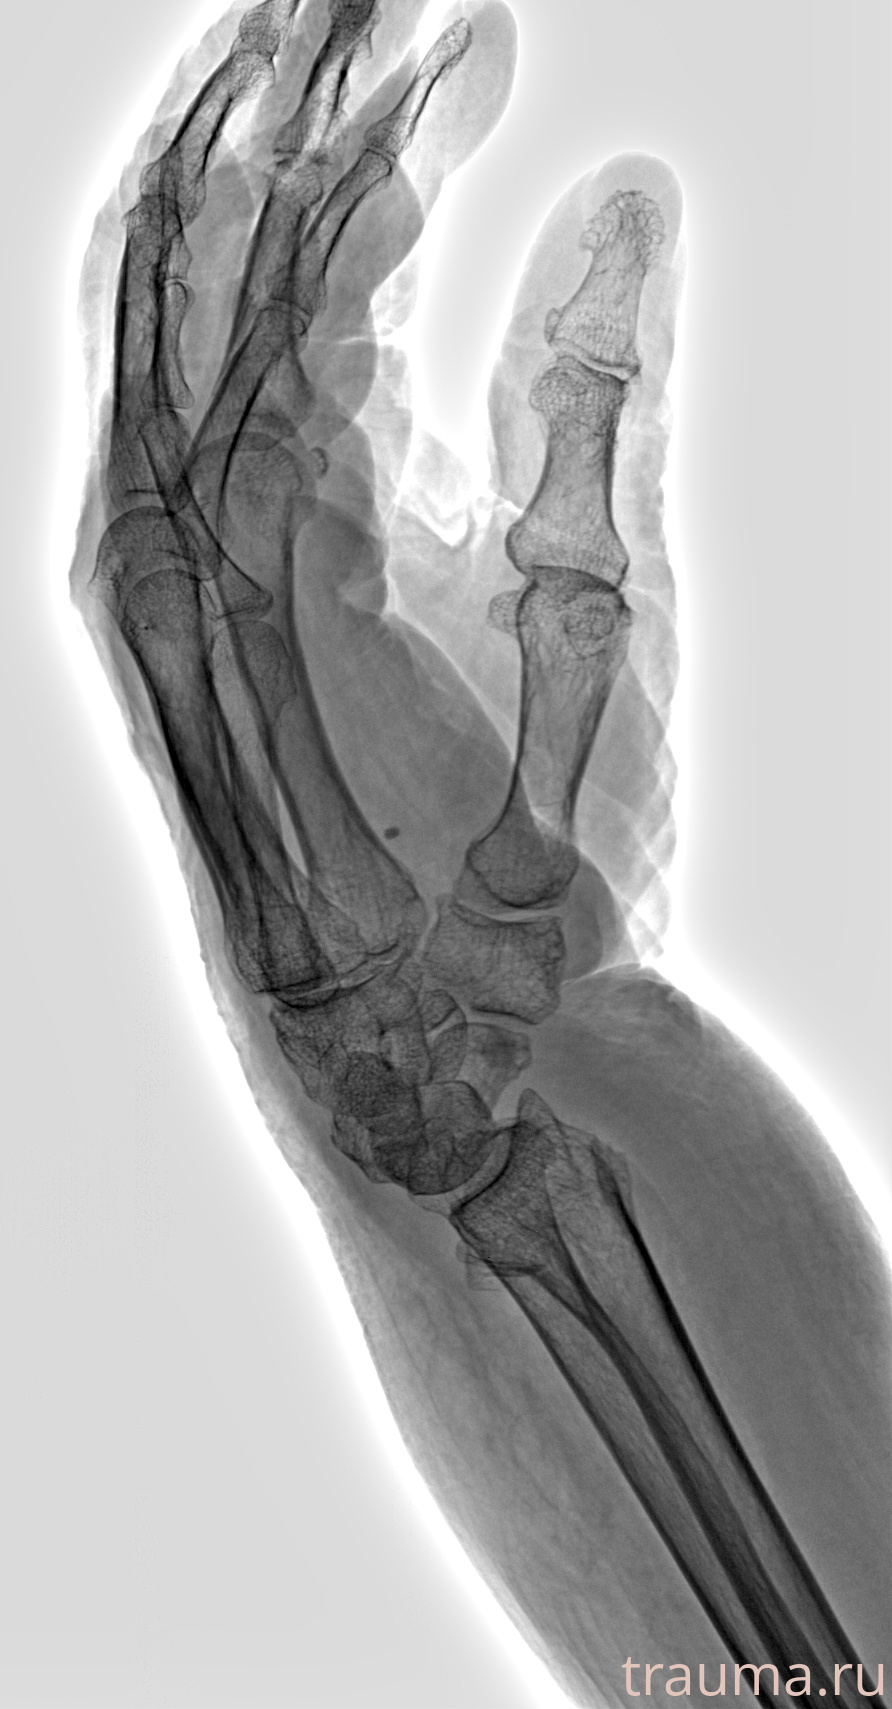

Рентгенограммы

Рентген на дому: по вашему адресу приезжает врач-рентгенолог, травматолог-ортопед с мобильным рентгеновским аппаратом, проводит диагностику травмы или заболевания, делает необходимые рентгенограммы, дает рекомендации по дальнейшему лечению. Получить качественные снимки в домашних условиях возможно благодаря уникальной методике, разработанной МосРентген Центром для института  Склифосовского